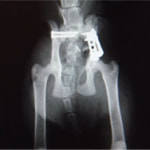

症例:交通事故による椎体脱臼

柴犬:9歳、避妊雌

交通事故直後、胸腰部に激しい疼痛、両後肢に完全麻痺を認め、シェフシェリントン徴候を呈していました。レントゲン検査において、第11-12胸椎間の脱臼が認められました。

脊髄の減圧、脊柱管の再構築・安定化を目的に、片側椎弓切除術およびMatrixMANDIBLE Plateによる椎体固定を実施しました。

隣接椎体を架橋するようにプレートを設置しました。

術後レントゲン写真